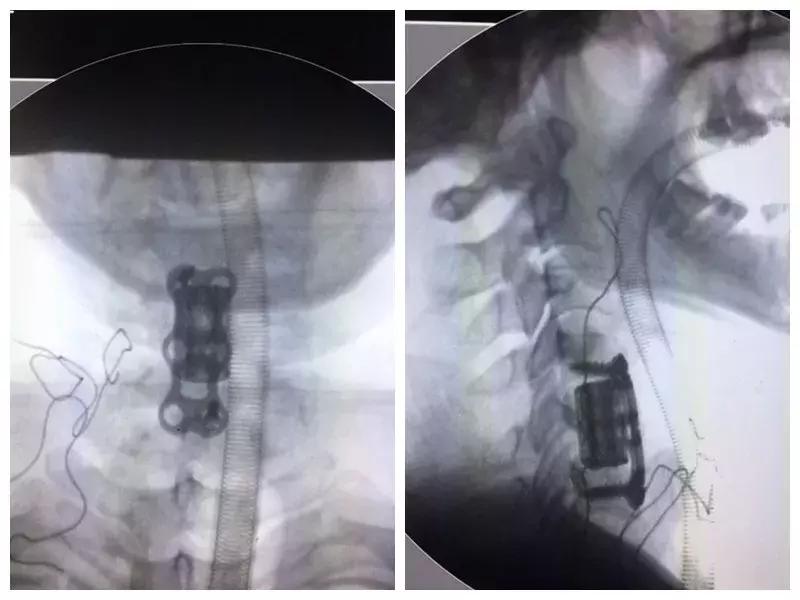

3D打印椎体的照片

术后照片